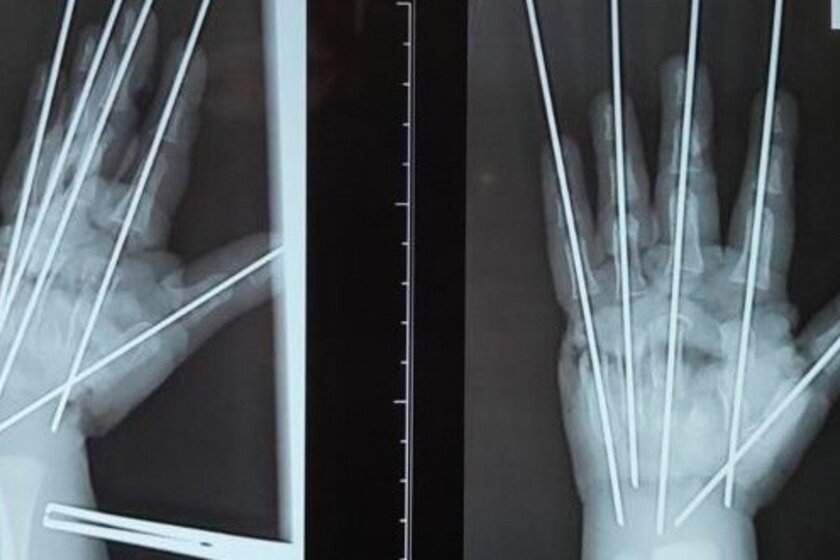

Врачи Петербургского педиатрического университета смогли спасти кисть двухлетнего мальчика, исследовавшего мясорубку. Об этом 4 сентября сообщает пресс-служба вуза. Двухлетний пациент из Псковской области получил тяжелейшую травму вечером в воскресенье, 3 сентября. Сотрудники МЧС извлекли его руку из механизма, а псковские хирурги направили ребенка в Петербург, где работает единственное на Северо-Западе детское микрохирургическое отделение. Малыша осмотрел дежурный микрохирург Антон Волков. – Травма очень тяжёлая, что обусловлено раздавливающим механизмом мясорубки. Повреждена была вся кисть, раздроблены кости, сухожилия, сосуды, нервы. Фактически имела место ампутация – кисть держалась на нескольких связках. Нашей задачей было сохранить жизнеспособные ткани, восстановить анатомию конечности и кровообращение, – сообщил врач. Специалисты буквально собрали по частям травмированную конечность и выполнили металлоостеозинтез, чтобы соединить осколки костей. Операция длилась более пяти часов

Специалисты буквально собрали по частям травмированную конечность и выполнили металлоостеозинтез, чтобы соединить осколки костей. Операция длилась более пяти часов. Сейчас пациент находится в отделении реанимации. Врачи не могут дать точный прогноз, но они сделали все возможное: восстановили кровоснабжение, и кожа на руке стала розоветь.